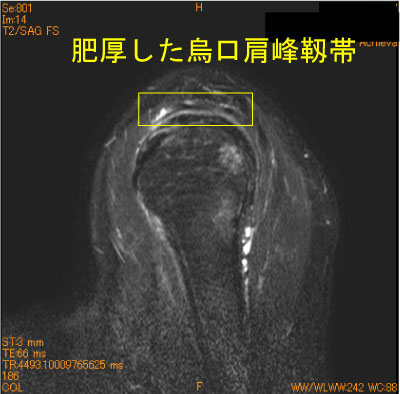

40代女性、バイオリン、ハープ奏者、 肥厚した烏口肩峰靭帯が棘上筋腱と滑液包側を擦っている。

棘上筋筋腹の脂肪抑制T2 high changeは筋浮腫の所見、慣れてくると各靱帯が同定出来る。

筋浮腫という病態がある。脂肪抑制T2WIは不可欠。